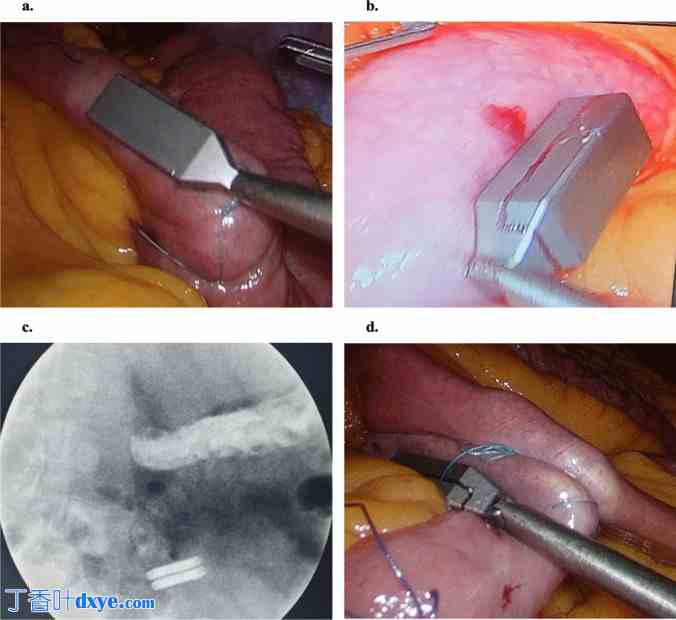

第一块(远端,回肠)腔内磁体被检测到超出特赖茨韧带。腔外定位装置的磁性端通过肠壁与磁体磁力连接(图 3a)。定位装置的长柄用于将磁体拉动或“滑行”至肠道,到达回肠标记处(图 3b)。吞咽的第二块磁体也同样滑行至目标空肠位置。如果发生肠痉挛,影响磁力冲浪,静脉注射解痉药物(例如布斯科潘)可能有助于缓解这一过程。

图 3.

腹腔镜磁力定位:a 将腔外磁力定位装置与第一个吞咽的(回肠)腔内磁体对齐,并“冲浪”至远端回肠的标记区域;b 将第二个吞咽的(空肠)磁体同样冲浪至近端空肠的标记区域;c 将两个磁体(位于肠袢内)靠近;d 用连续缝线缝合两侧肠袢的肠系膜,以防止内部疝出。

内镜医师将连接到内镜输送系统的第二块(近端,空肠)磁体通过柔性内镜的工作通道输送至特赖茨韧带以外。腹腔镜摄像机可以看到肠腔内内窥镜发出的光线(图4)。第二块磁铁与其内窥镜输送系统分离,并通过磁力连接到腔外定位装置。内窥镜医师取出内窥镜,吸出肠钳上方十二指肠内的大部分充气,并撤出内窥镜器械。然后松开肠钳,在腹腔镜控制下将第二块磁铁送至近端标记的空肠袢。

图4

使用柔性内窥镜将第二块磁铁或两块磁铁(如果无法吞咽)定位到特赖茨韧带之外。肠腔内内窥镜发出的光线可通过腹腔镜摄像机看到